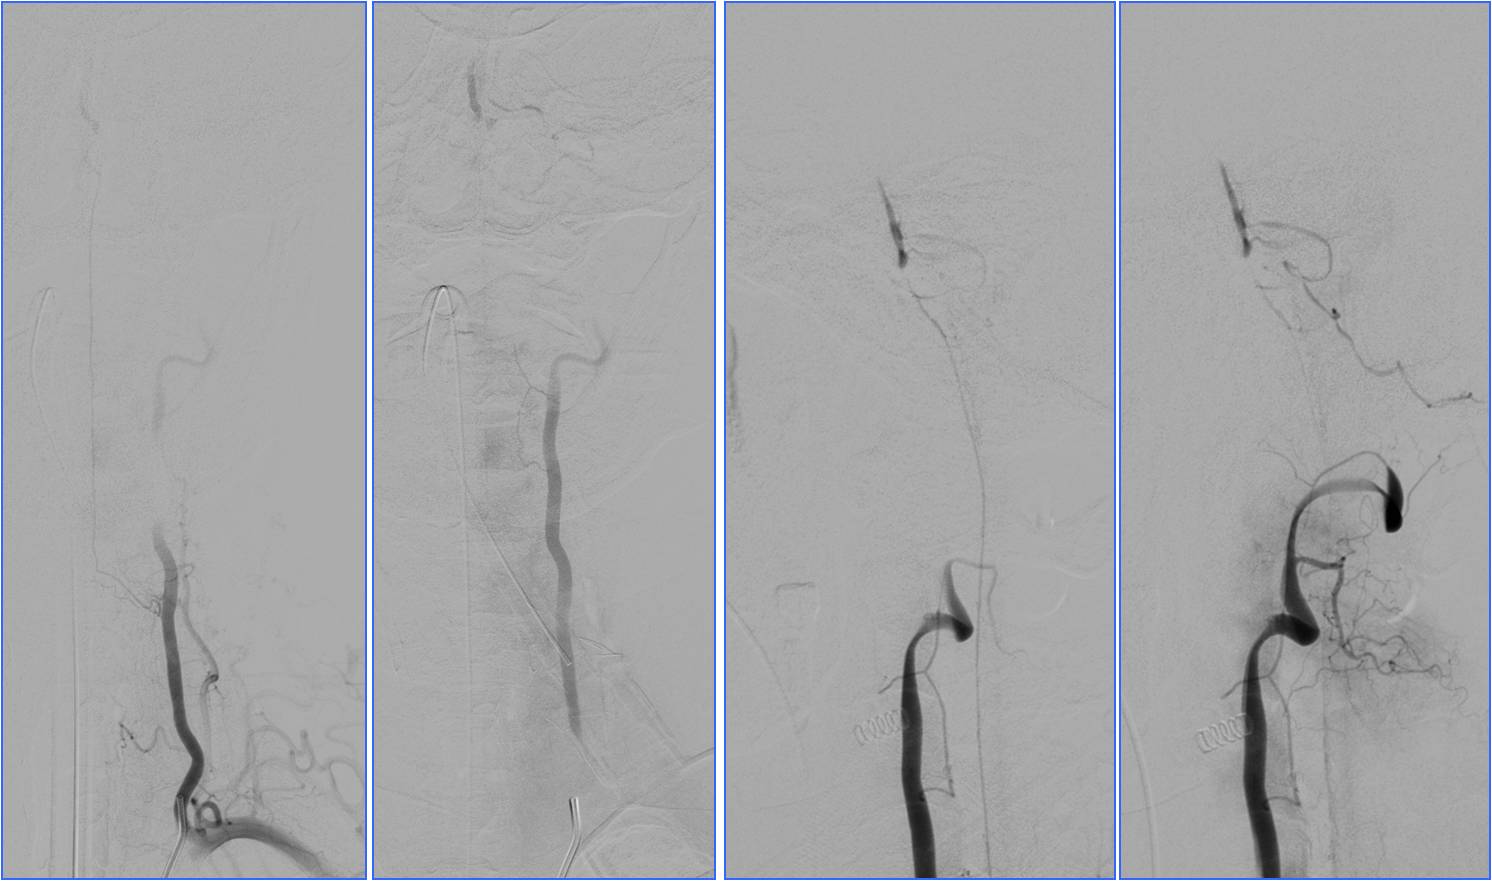

Case2 ICA起始部支架置入

》男,56岁。既往有高血压病及吸烟史。

》因 “言语不清5小时,加重伴左侧肢体无力1小时”于16:30入院。

》查体:血压150/100mmHg。嗜睡,不完全运动性失语,左侧中枢性面舌瘫,左侧肢体肌力0级,左侧巴氏征阳性。NIHSS评分15分。

》头CT(17:00)示右侧大脑中动脉M1及M2段高密度征。

》17:50给予阿替普酶静脉溶栓,5mg静推,余45mg持续泵入。

》18:00家属同意行急诊DSA+血管内治疗。

》18:30股动脉穿刺。

》20:30结束手术,送神经内科ICU,给予丙泊酚泵入镇静(持续24小时),乌拉地尔持续泵入控制血压在110/70mmHg左右。

》48小时后转入普通病房,NIHSS评分4分。

》13天出院, NIHSS评分3分。

▼右侧大脑中动脉高密度征

▼M2段栓子

▼将微导管置于右侧大脑中动脉M1段远端,缓慢注入5mg阿替普酶,5分钟后造影见局部血管再通,远端分支显影良好。